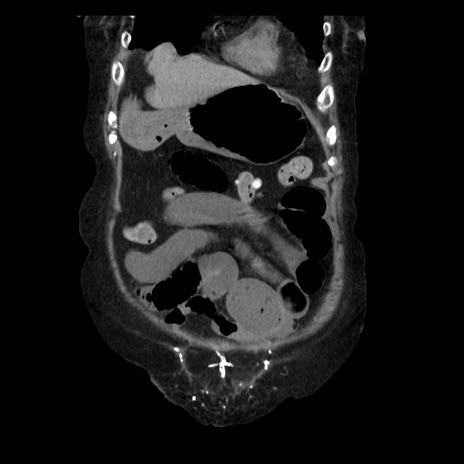

症例14(冠状断像)

【症例】 90歳代女性

【主訴】 腹痛・嘔吐

【現病歴】今朝から左側腹部痛を認めた。 経過観察していたが、嘔吐を認めたため来院。

【既往歴】 子宮癌術後

【身体所見】 意識清明、BP 127/54mmHg、P 98bpm Sp02 95%(RA)、BT 35.8°C、腹部平坦・軟腸ぜん動音聴取良好、右下腹部圧痛(+) 反跳痛なし

【データ】WBC 9800、CRP 0.46